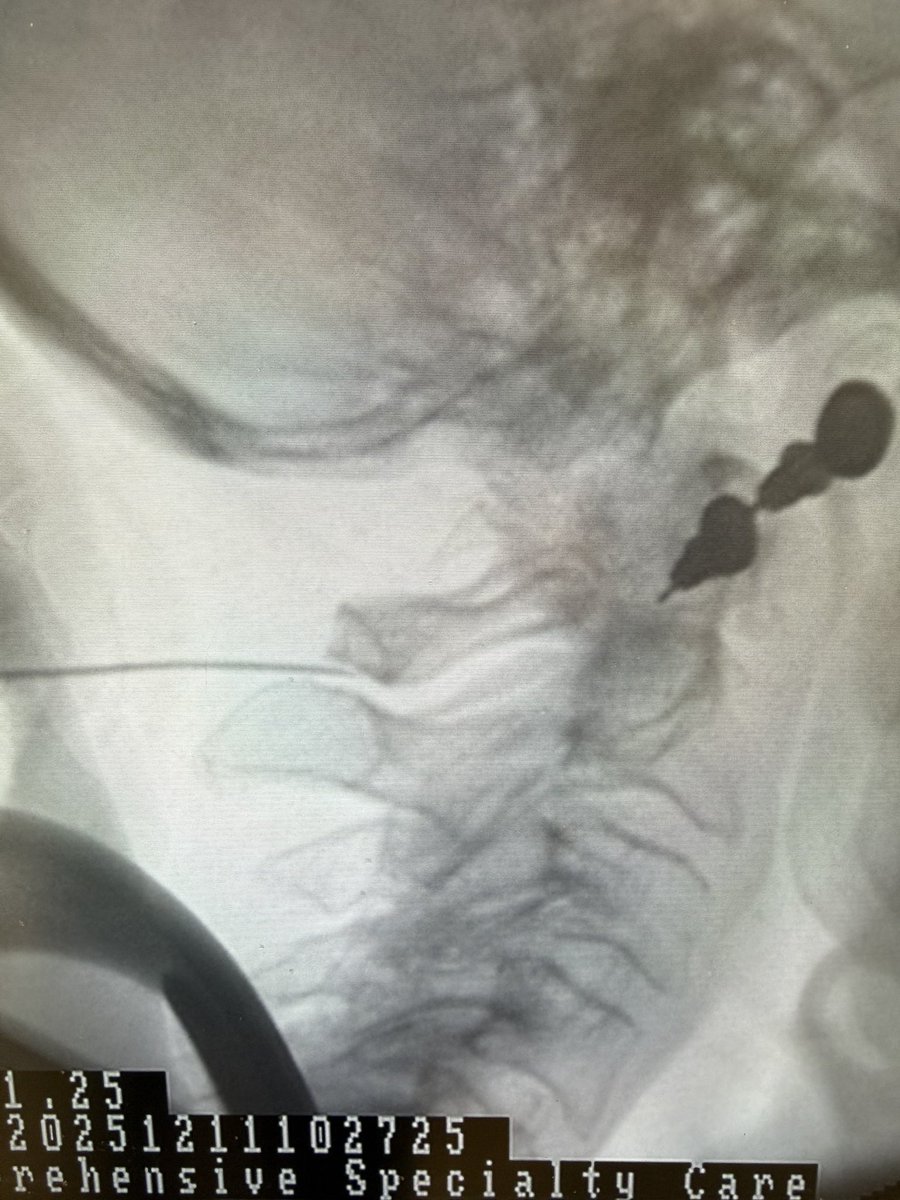

Interesting case of C1 – 2 interspinous bursitis treated with an injection of local anesthetic and steroid anti-inflammatory. Very effective treatment in this case.